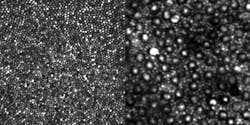

Though earlier AO systems could effectively image cones and have become a mainstay of high-resolution retinal imaging research, the smaller rods, which outnumber cones 20 to 1 in the retina, have eluded clear and contiguous observation in the living eye.

The design of the AO instrument that led to clearly visualizing rods was, according to Dubra, “embarrassingly simple, and relied on well-known equations and concepts.” By simply folding the spherical mirrors that act as lenses in the instrument into a three-dimensional structure, the image quality of the retina was improved sufficiently to clearly resolve the contiguous rod mosaic, as well as the entire cone mosaic at the foveal center. Dubra and his colleagues were able to push the device’s resolution to its optical limits of nearly 2 µm, or the approximate diameter of a single rod in the human eye.